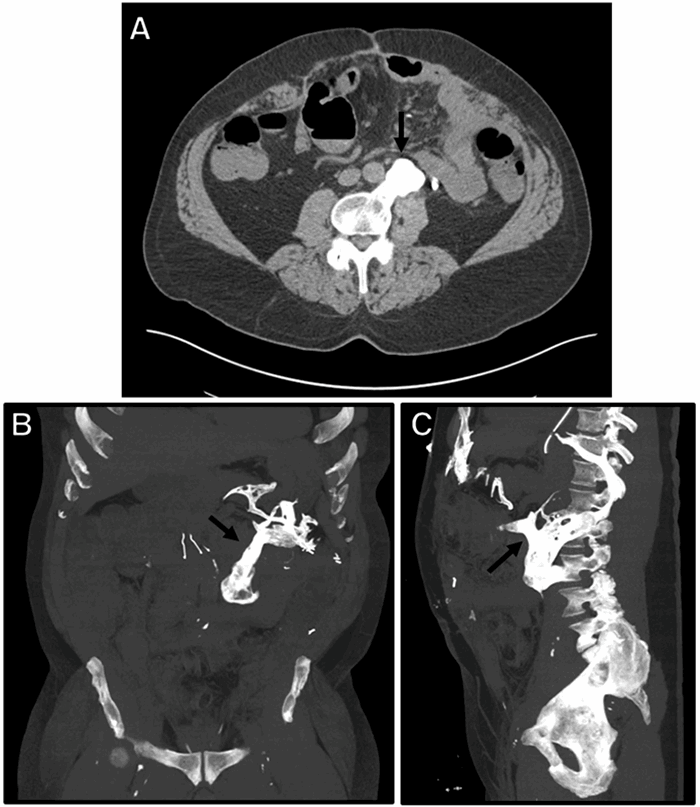

Several years later, the patient reported a three-day period characterized by diffuse abdominal pain, anorexia, nausea, vomiting, and no bowel movements. Upon arrival to the tertiary care center, the patient endorsed persistent abdominal pain. On physical exam, his abdomen was diffusely tender in all quadrants and high-pitched bowel sounds were present. A CT scan of the abdomen and pelvis with IV contrast demonstrated a focal segment of small bowel dilated to 4.4 cm, with a discrete transition point consistent with SBO (Figure 1). The CT also revealed an osseous projection arising anteriorly from the L3 vertebral body that joined with an osseous projection from the inferior left T12 rib and formed a pseudoarthrosis in the abdomen from a third projection—this third projection arose from the sternum/xiphoid process (Figure 2 and Figure 3) This finding was suggestive of trauma-related heterotopic ossification (HO)—indeed, this ossification wrapped around the small bowel (Figure 1A) and provided a clear potential for obstruction. A ventral hernia was also noted on imaging but did not appear to be the cause of the patient’s SBO. The patient was unaware of the ossification and denied chronic abdominal pain that might be related to the ossification.

Figure 1. Representative axial (A) and sagittal (B) CT images of abdomen, demonstrating dilation of small bowel to 4.4 cm within a ventral hernia sac (double white arrow) with a distinct transition point (single white arrow), consistent with low-grade small bowel obstruction.